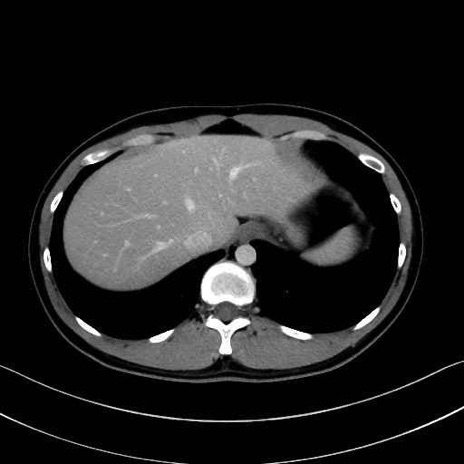

腰方形筋(quadratus lumborum muscle)のCT画像の解剖

1. 体幹部(腹部・背部・後腹壁)の筋肉

腰方形筋 (Quadratus lumborum)